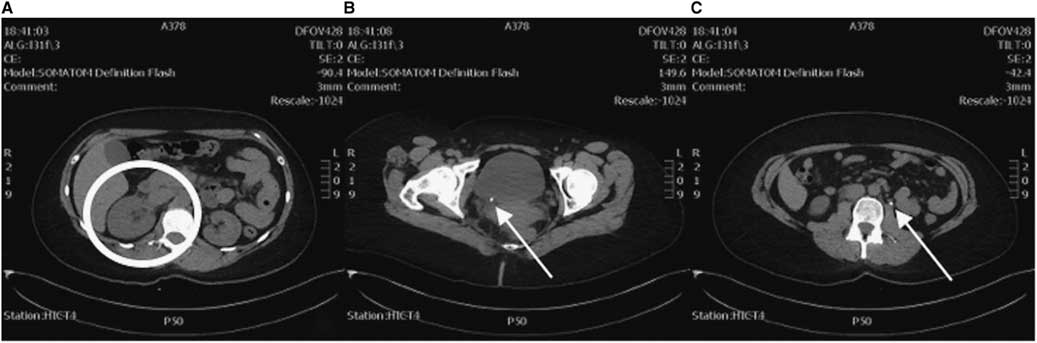

As the clinical course (demonstrated by intractable flank pain) failed to improve over 5 hours with symptomatic therapy and the diagnosis of renal colic yet to be confirmed, an abdominal and pelvic CT was ordered. This study revealed a small 5-mm distal obstructing ureteric calculus at the right vesicoureteric junction causing proximal moderate hydroureteronephrosis (Figure 2). Coincidentally, the CT also revealed another 5-mm left proximal ureteric calculus at approximately the level of the L3 vertebra causing mild ipsilateral proximal hydroureter.

Figure 2 CT axial views. A) Enlarged right kidney indicative of hydronephrosis (circle) compared to the left. B) A 5-mm right distal ureteric calculus at the right vesicoureteric junction (arrow). C) A 5-mm left proximal ureteric calculus (arrow).